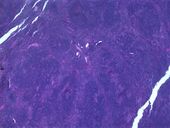

سرطان الغدد الليمفاوية، لاحظ المعالم غير المنتظمة للنواة كما تُظهر الخلايا CD5 ،CD20 والسيكلين D1 بصبغة الهيماتوكسيلين والإيوسين

اُستخدمت العديد من التصنيفات السابقة، بما في ذلك رابابورت 1956، كييل 1974، وREAL 1994. وكانت تلك التصنيفات تستبعد لمفوما هودجكين وتقسم الأورام اللمفاوية المتبقية إلى أربع درجات (منخفضة، متوسطة، عالية، والمتنوعة) اعتمادًا على تقدم المرض، مع بعض التقسيمات الفرعية على أساس حجم وشكل الخلايا المصابة. ولكن لم تشمل هذه التصنيفات أي معلومات حول علامات سطح الخلية، أو علم الوراثة، ولم تضع أي تمييز بين الأورام اللمفاوية في الخلايا T والأورام اللمفاوية في الخلايا B. كانت من قبل مقبولة على نطاق واسع، أما الآن فلم تعد تُستخدم. إلا من قِبل بعض وكالات السرطان لجمع الإحصاءات عن سرطان الغدد الليمفاوية والمقارنات التاريخية.[29]